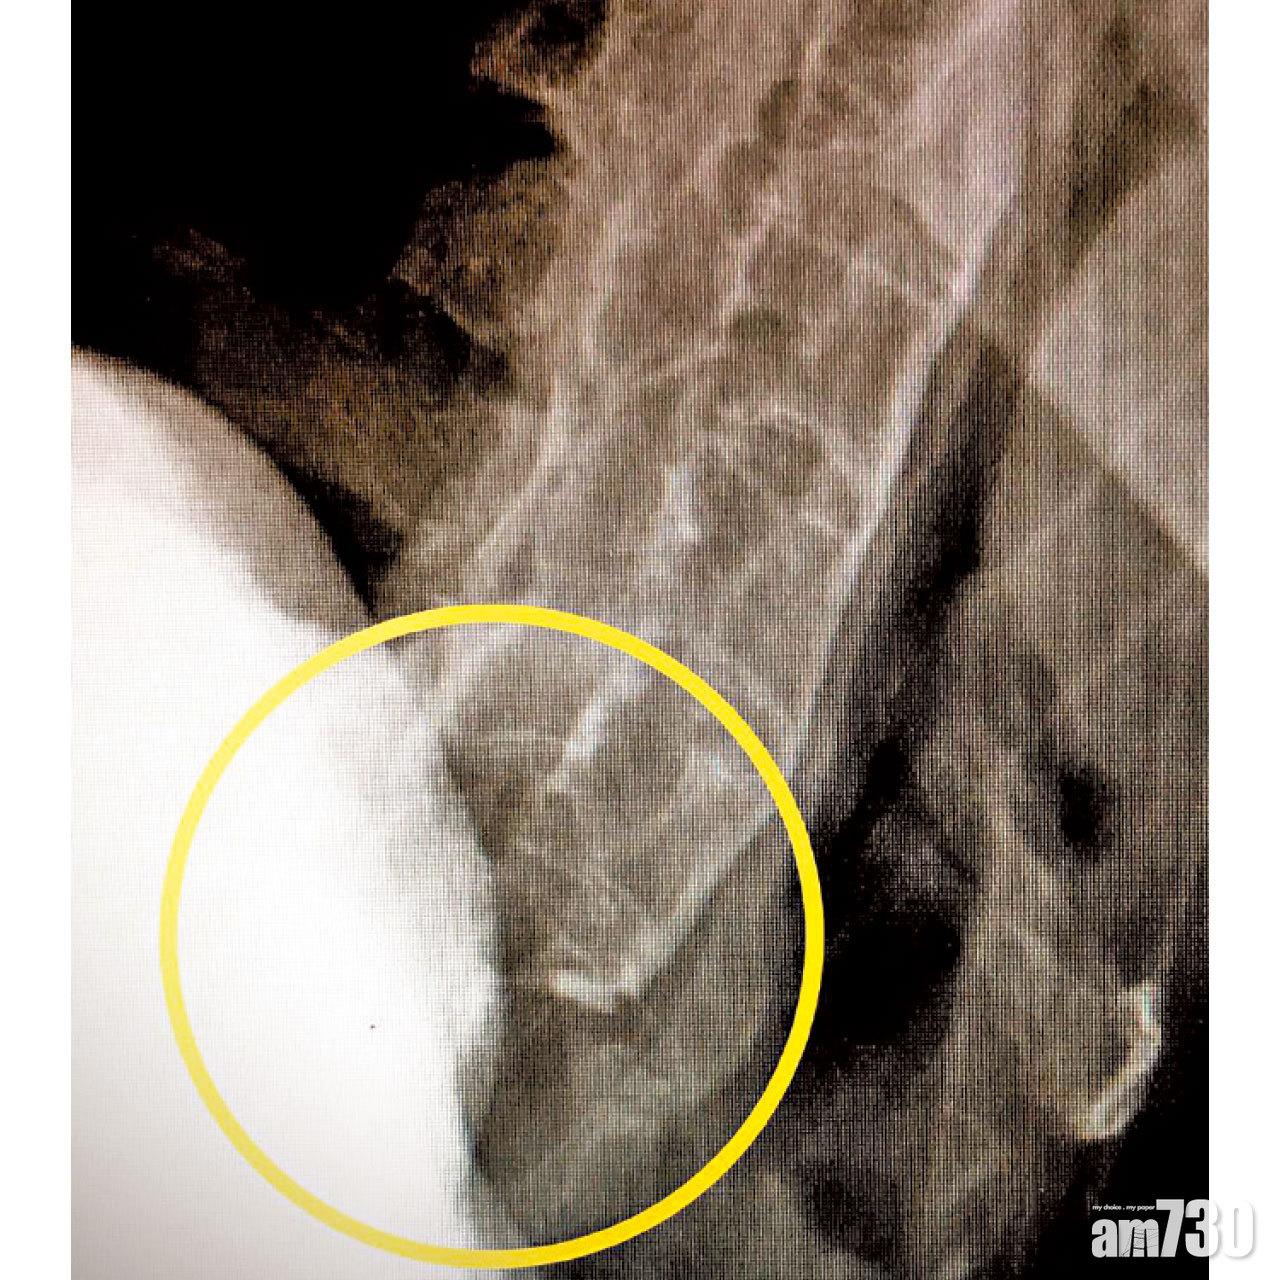

林:「咁如果由腰到頸都硬到不得了,甚至唔可以抬起頭向前看,依個病又叫做?」曾:「要排除係強直性脊椎炎,佢係自體免疫性疾病嘅一種,患者通常係男性,後生開始發病,主要影響中軸骨骼,造成慢性關節炎。起初腰背痛同僵硬會持續3個月,到後期中軸關節會逐漸融合。當頸椎關節融合而變得僵硬,頸椎就變成咗一條長骨,萬一唔小心跌倒就會導致頸椎骨折。」